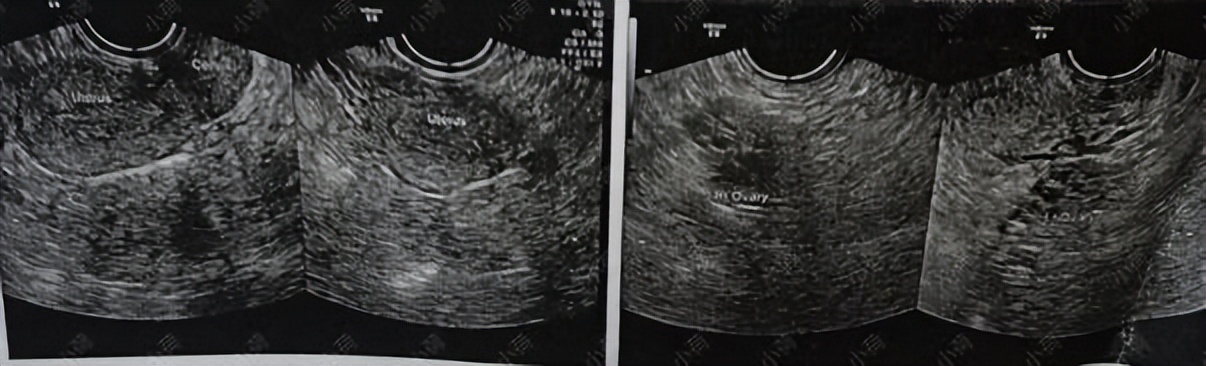

了解她的情况之后我让她去化验血,检查一下激素六项+β人绒毛膜促性腺激素,以排除怀孕;再做一个经阴道B超。

结果显示: 多囊卵巢综合征,激素紊乱 。

图片来源 :讲述者提供